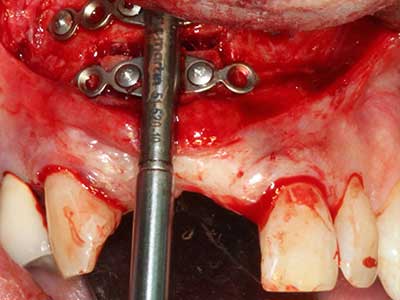

Fig. 28: During removal of metal, the basal chin regions are separated with the Piezomed while retaining the lingual blood supply.

Fig. 29: Forward displacement of the chin by 5 mm and fixation with two osteosynthesis plates (KLS Martin). The two mental nerves can be detected in the marginal region.

Fig. 30: The aesthetic improvement in the chin contour after the operation can be clearly seen.